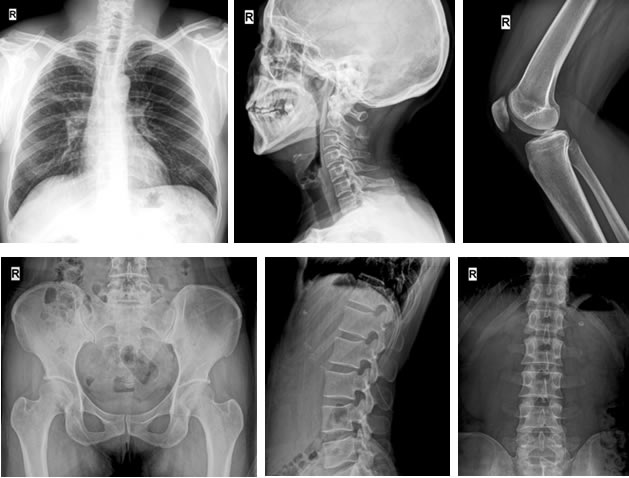

With the ergonomic consideration of design, the system provides much more patient-oriented applications by using mobile detector. By the application of unique ‘Level’ post- processing software, the image details is optimized and enhanced for clinical diagnosis. Through the intuitive, multilingual user interface and post processing flow, the end-user is guaranteed to get the premium images more efficiently and avoids the retake time-waste.

The unique ‘iStitch’ function extends the application of panoramic view digital radiographic image, like whole spine or long-bone image. By one-button pushing, the system can finish the whole imaging process automatically without any other additional operation.